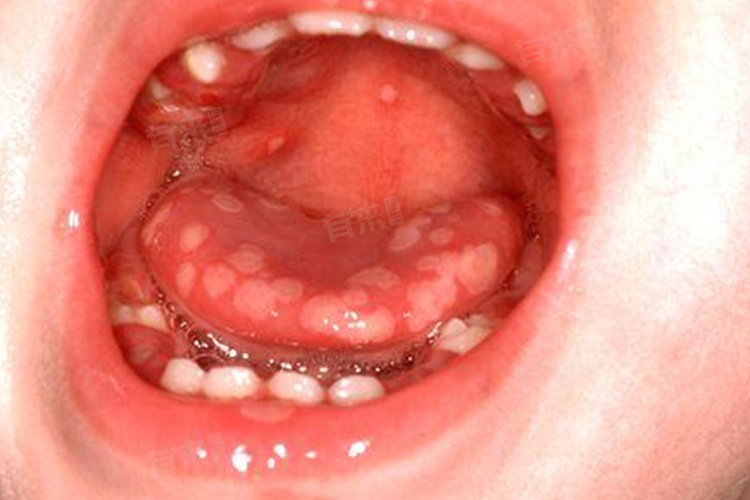

儿童舌头上溃疡的治疗方法多样,主要包括冰敷、淡盐水漱口、局部用药等方式,应根据病情和症状选择合适的方式。在治疗过程中,家长应密切关注儿童的症状变化,及时就医并遵医嘱进行治疗。

3、局部用药:在溃疡部位直接涂抹药物是快速缓解疼痛和促进愈合的有效方式,可以选择使用冰硼散、口腔溃疡散等药物,此类药物具有消炎、止痛、收敛、促进溃疡面愈合的作用。